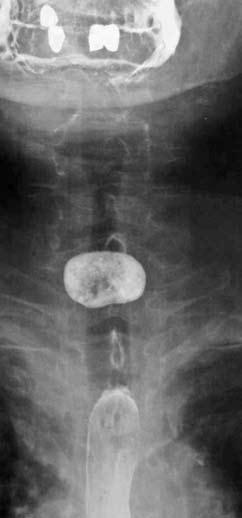

Основным методом диагностики ДП до сих пор остается рентгенологический. Применяют контрастную рентгеноскопию и рентгенографию пищевода в разных проекциях (полипозиционное исследование). При этом определяют локализацию, размер и форму дивертикула, характер компрессии пищевода заполненным мешком. При рентгенологическом исследовании органов грудной клетки – признаки аспирационных легочных осложнений. Рентгенограммы пищевода при дивертикулах различной локализации представлены на рисунках 35–37.

Рис. 36. Рентгенограмма пищевода при бифуркационном дивертикуле

Рис. 37. Рентгенограмма пищевода при эпифренальном дивертикуле